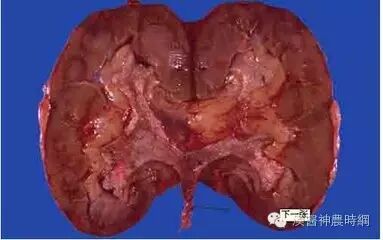

肾功能不全

肾功能不全是由多种原因引起的,肾小球严重破坏,使身体在排泄代谢废物和调节水电解质、酸碱平衡等方面出现紊乱的临床综合症候群。分为急性肾功能不全和慢性肾功能不全。预后严重,是威胁生命的主要病症之一。

肾功能衰竭

肾脏功能部分或全部丧失的病理状态。按其发作之急缓分为急性和慢性两种。急性肾功能衰竭系因多种疾病致使两肾在短时间内丧失排泄功能,简称急性肾衰。